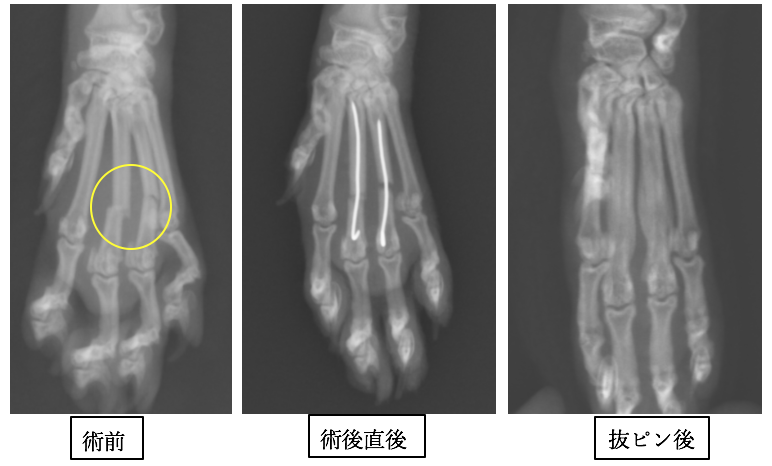

中手骨骨折の実際の症例

子猫の指で0.6mmという最も細いピンを入れています。